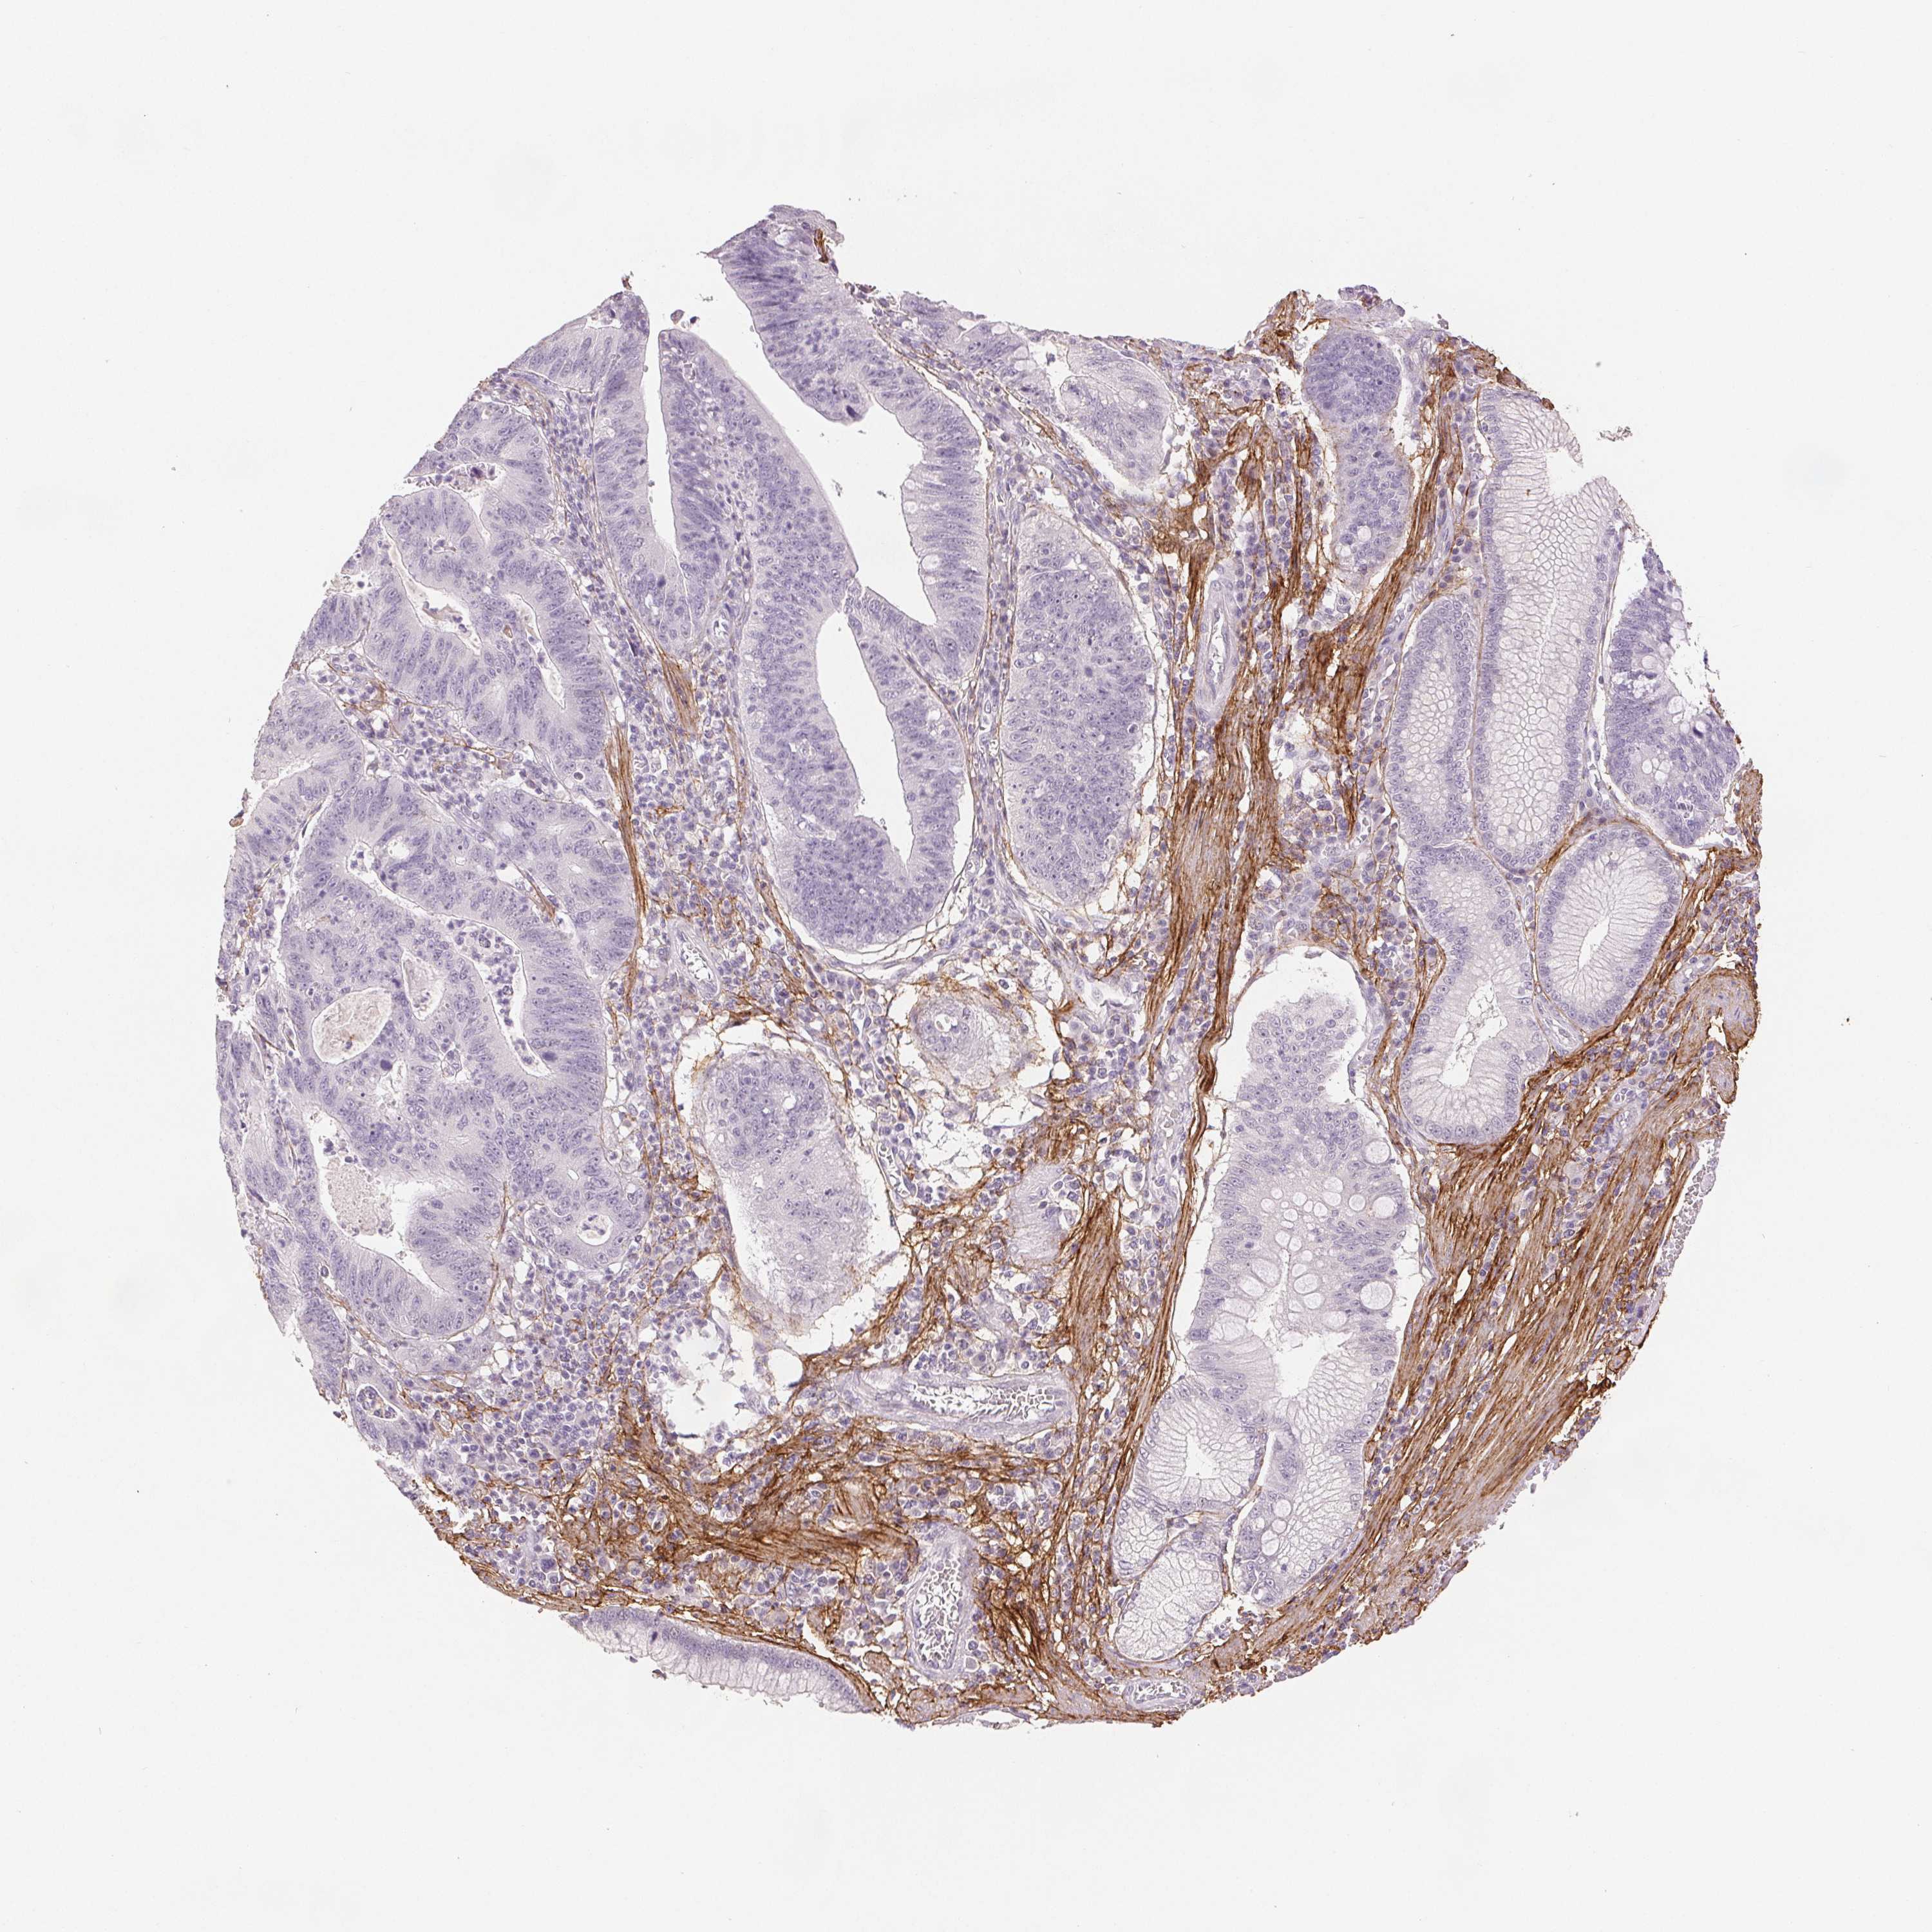

STOMACH CANCER - Protein expressioni

A mouse-over function shows sample information and annotation data. Click on an image to view it in a full screen mode. Samples can be filtered based on level of antibody staining by selecting one or several of the following categories: high, medium, low and not detected. The assay and annotation is described here.

Note that samples used for immunohistochemistry by the Human Protein Atlas do not correspond to samples in the TCGA dataset.

Antibody stainingi

Antibody staining in the annotated cell types in the current human tissue is reported as not detected, low, medium, or high, based on conventional immunohistochemistry profiling in selected tissues. This score is based on the combination of the staining intensity and fraction of stained cells.

Each image is clickable and will lead to virtual microscopy that enables deeper exploration of all samples and also displays staining intensity scores, fraction scores and subcellular localization as well as patient and tissue information for each sample.

HPA017759

HPA021057

CAB002670

CAB058696

CAB068188

CAB080202

Staining

High

Medium

Low

Not detected

Intensity

Strong

Moderate

Weak

Negative

Quantity

>75%

75%-25%

<25%

None

Location

Nuclear

Cytoplasmic/membranous

Cytoplasmic/membranous,nuclear

Adenocarcinoma, NOS

Adenocarcinoma, High grade